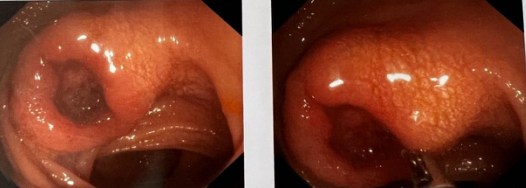

年过中旬的乔先生近30年来饱受大便习惯伴性状改变的困扰,大便不成形、稀,频次多、量少,偶有大便带血,色暗红。到医院做电子肠镜等相关检查后,发现肠腔已经明显狭窄,更没想到同时检查出了乙状结肠肿块,但是乔先生自己感觉一点征兆也没有,怎么一个月突然就得了结肠癌呢?

betway在线登陆普通外科张健主任介绍,结肠癌是常见的发生于结肠部位的消化道恶性肿瘤。大多数结直肠癌早期没有症状,像乔先生这种前期除了出现腹痛胃胀情况外也没感受到任何不适,直到突然发现自己便血情况才发现该病。

经过全面的检查和评估,张健主任最终决定,根据患者的具体情况,为其制定和实施个体化的精准治疗快速康复方案。在相关科室的密切配合下,由张健主任带领普通外科团队为乔先生成功实施了腹腔镜下乙状结肠癌根治术。在普通外科医护人员的精心护理下,乔先生恢复迅速,术后11天顺利出院。

结肠肿瘤目前已经成为我国第二高发的恶性肿瘤,多见于中老年人,50岁以后到70岁左右是结肠肿瘤的高发年龄阶段。早期通过腹腔镜进行根治性手术切除是结肠癌治疗的方法,需要着重强调的是,个体化精准治疗是高风险病人救治成功的关键。